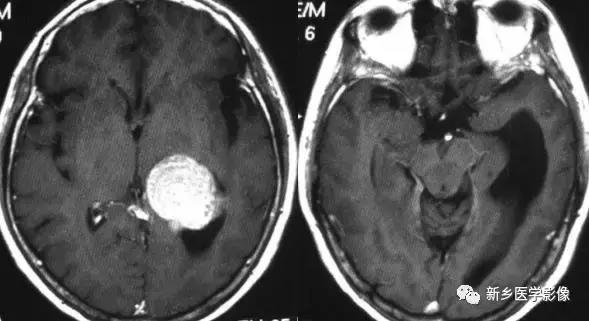

4.一侧室间孔阻塞

脑脊液主要产生于脑室的脉络膜丛。当一侧室间孔阻塞时,同侧侧脑室脉络膜丛产生的脑脊液不能进入三脑室,脑脊液在侧脑室内聚积,CT和MR检查表现为一侧侧脑室扩大,扩大明显时可有中线结构向对侧移位,主要原因有室间孔附近的肿瘤、囊肿、囊虫及炎性粘连。确定一侧侧脑室扩大为室间孔阻塞所致的要点包括:一侧侧脑室扩张明显,有张力.透明隔向对侧移位;扩一大的侧脑室周围没有能够导致该侧侧脑室扩大的其他可以解释的原因。